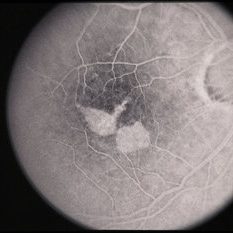

---thumb.jpg/image-square;max$300,300.ImageHandler) Age Related Macular Degeneration - Geographic Atrophy

Age Related Macular Degeneration - Geographic Atrophy

May 3 2013 by Suber S. Huang, MD, MBA, FASRS

Geographic Atrophy.

Imaging device: Retina Diseases Imaging Analysis Reading Center

Condition/keywords: advanced geographic atrophy, atrophic scar, atrophic spot, geographic atrophy, macula lesion, pigment epithelial atrophy